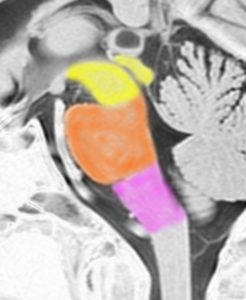

これは脳の中心部を縦切りにした写真です。脳幹部は上から順に,中脳 midbrain (黄色),橋 pons(オレンジ),延髄 medulla oblongata(ピンク)と呼ばれます。